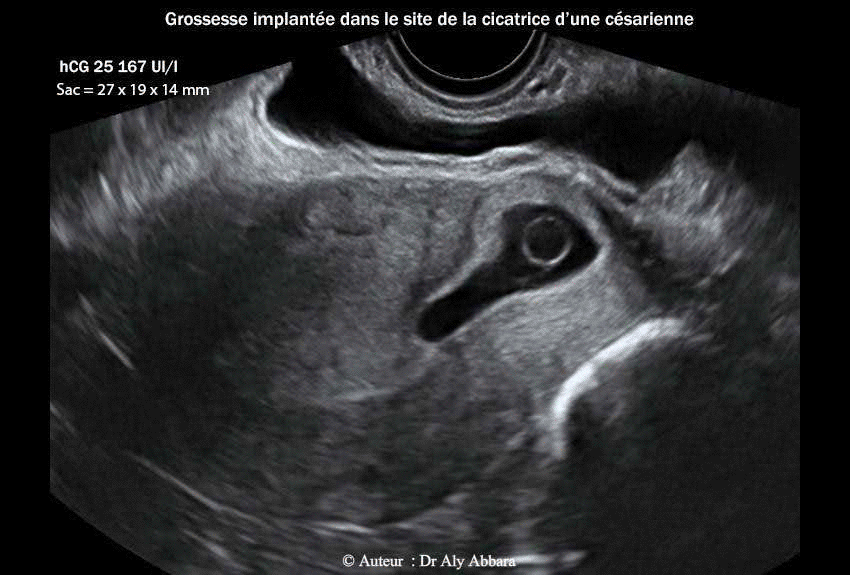

• Images échographiques par voie endovaginale montrant un sac gestationnel d'une grossesse débutante et partiellement intramurale, implantée dans le site de la cicatrice de l'hystérotomie segmentaire transversale d'une ancienne césarienne.

• L'aspect du sac gestationnel au 4e jour post traitement médical par méthotrexate : il mesure 27 x 19 x 14 mm de diamètres (= 3,7 cm3) ; le dosage de β-hCG plasmatique était égal à 25 167 UI/l ; devant l'augmentation de ce taux, une deuxième dose méthotrexate (75 mg) fut adminsitrée.

• A ce stade de l'évolution du sac gestationnel, le tissu trophoblastique envahit la paroi antérieure de la zone isthmique de l'utérus et devint en contact avec la paroi vésicale contiguë (trophoblaste percreta).

Le 04.10.2012 (5+2 SA) -J0- : la patiente consulte aux urgences pour légère douleur pelvienne sans métrorragie ; l'examen clinico-échographique permet de mettre en évidence le diagnostic d'une grossesse débutante implantée dans le site de l’ancienne cicatrice de l’hystérotomie segmentaire transversale de l'ancienne césarienne ; il s'agissait d'un sac gestationnel de (20 x 12 8,5 mm) de diamètre, contenant une vésicule vitelline sans image embryonnaire.

A J4 (08/10/2012) ; devant l'augmentation excessive du taux de hCG plasmatique : 25 167 UI/l (> 25 % comparé au taux du J0), elle a été administrée par voie intramusculaire une 2ème injection de méthotrexate (75mg).

A ce stade de l'évolution du sac gestationnel, on constate la présence d'une invasion totale, par le tissu trophoblastique, de la paroi antérieure de la zone isthmique de l'utérus ; ce tissu trophoblastique devint en contact direct avec la paroi vésicale juxtaposée ; puis à environ 4 semaines post traitement médical, le Doppler montre la formation de micro-vaisseaux sanguins pénétrant verticalement de tissu trophoblastique vers la paroi vésicale contiguë. L'ensemble de ces signes échographiques évoque le diagnostic ultra précoce de trophoblaste percreta